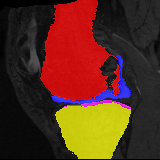

Moving

Target

Mono-0

Mono-5

DA-1

DA-5

Mono-200

Results: All trained networks are evaluated using Dice overlap scores between predictions and the manual segmentations for the segmentation network, or between the warped moving segmentations and the target segmentations for the registration network. Tabs. 1 and 2 show results for the knee and brain MRI experiments respectively in Dice scores (%). Fig. 2 shows examples of knee MRI registrations and brain MRI segmentations.

Qualitative results: DA achieves more anatomically consistent registrations than the mono-networks on the knee (Fig. 2) and Brain MRI samples (see supplementary material).